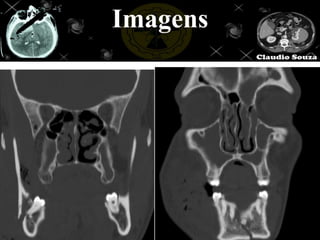

Imagens